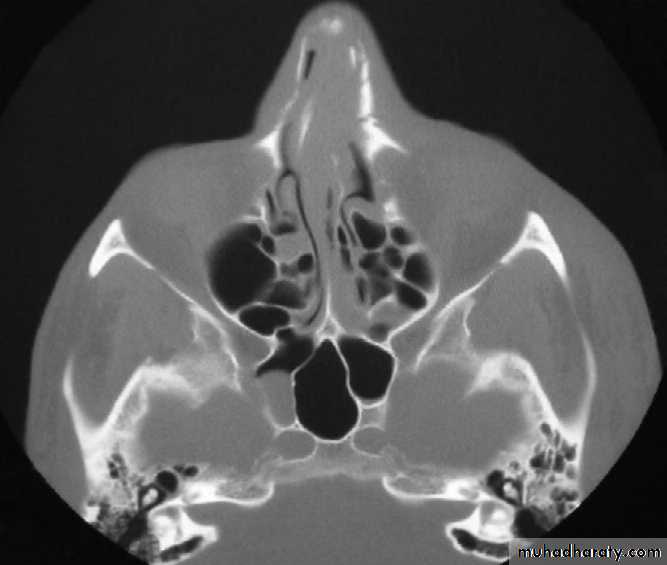

Computed TomographyCT is the gold standard for radiographic evaluation of zygomatic fractures. Axial and coronal images are obtained to define fracture patterns, degree of displacement, and comminution and to evaluate the orbital soft tissues.

Bilateral comminuted nasal bone fractures and septal deviation following motor vehicle collision.